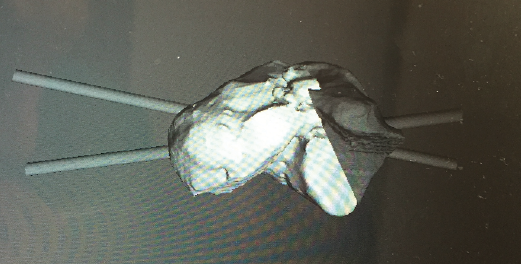

- Diseño de la guía de corte guiada por aguja de Kirschner (Figura 12).

- Colocación de la guía intraoperatoria sobre relieves óseos (Figura 13).

- Resección intraoperatoria (Figura 14).